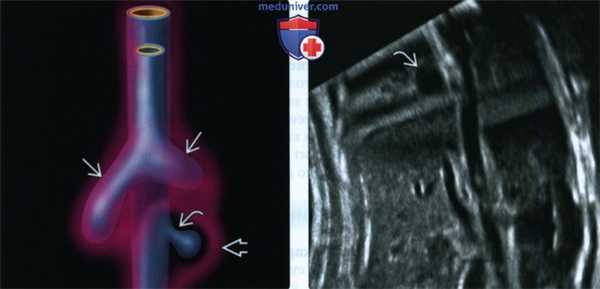

(Слева) Предположительный патогенез бронхогенной кисты. В отличие от нормально развивающихся бронхов патологический добавочный вырост передней кишки не взаимодействует с окружающей эмбриональной мезенхимой (отмечена розовым цветом). Вырост, как правило, разобщается с первичной кишкой, в результате чего образуются слепо оканчивающийся мешок или киста.

(Справа) УЗИ во фронтальной плоскости. Непосредственно над диафрагмой видна расположенная по центру однокамерная киста.

2. УЗИ при бронхогенной кисте у плода:

• Простая однокамерная киста:

- Редко - многокамерная

• Практически всегда солитарная

• Может содержать гиперэхогенный детрит и не иметь четких границ с окружающими тканями

• Может сдавливать пищевод или близлежащие бронхи, особенно при крупных размерах:

о При выраженном сдавлении пищевода может развиться многоводие

о Обструкция бронхов приводит к перерастяжению и повышению эхогенности сегмента легкого дистальнее места обструкции вследствие накопления жидкости:

- Внешний вид может соответствовать картине объемного образования в легком

• При ЦДК кровоток не определяется